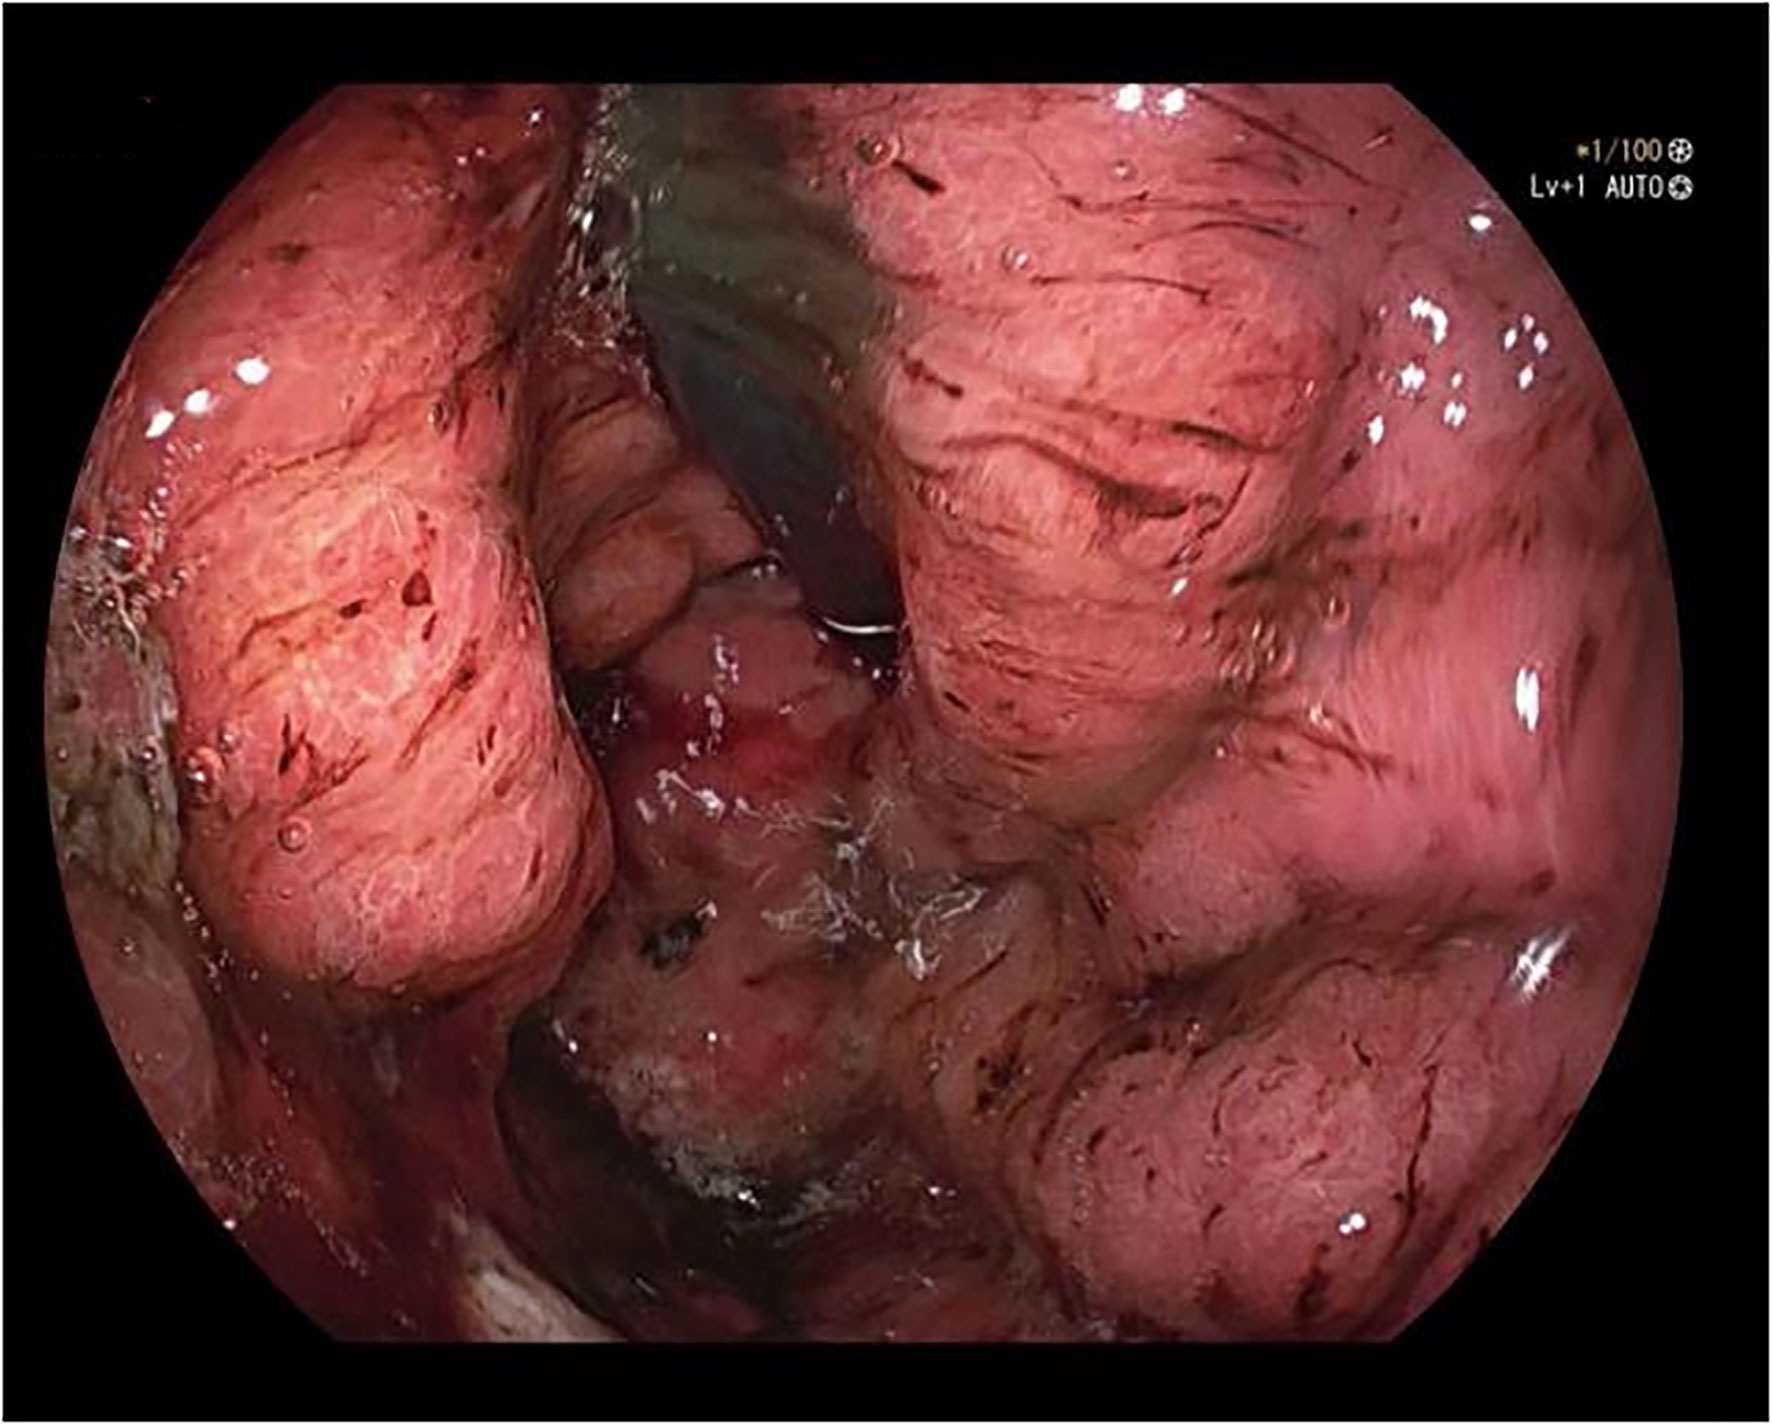

A 50-year-old male was admitted to the hospital due to abdominal distension and poor appetite. Laboratory examination results show that hemoglobin of 62 g/L, albumin of 32.2 g/L and the stool routine occult blood test was weakly positive. In order to further clarify the cause, the patient was examined by gastrointestinal endoscopy. Gastrointestinal endoscopy showed that the whole gastric mucosa was nodular hyperplasia, protuberance, densely distributed, and clustered locally, mainly in the fundus of the stomach. Massive hyperplasia lesions were removed at the endoscopic mucosal resection (EMR) of gastric body lesions for examination. A mass of nodular hyperplasia was found in the fundus of the stomach, and the structure of the top gland was lost. Two biopsies were taken. A large diverticulum can be seen in the descending colon, with smooth mucosa, and no bleeding, erosion, ulcer or other lesions are found. A pedunculated polyp of 1.0*2.0 cm in size can be seen in the sigmoid colon. The surface mucosa was congestive and edematous with erosion. A snare device was used to snare, and high-frequency electric resection was performed. The other colonic and rectal mucosa were smooth, with clear vascular texture and no obvious abnormalities. Figures 1–4 show the patient’s condition under a gastroscope. Pathological findings suggest the following: 1. (gastric fundus biopsy) mucosa high-grade intraepithelial neoplasia; 2. (gastric biopsy) juvenile polyps (Figure 5); 3. (sigmoid colon biopsy) Low-grade tubular adenoma with clean margins. Immunohistochemical results showed CK8/18 (+), Ki-67 (+50%), P53 (-, mutant), and HP (–).